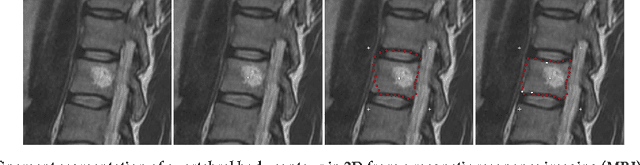

In this contribution, a semi-automatic segmentation algorithm for (medical) image analysis is presented. More precise, the approach belongs to the category of interactive contouring algorithms, which provide real-time feedback of the segmentation result. However, even with interactive real-time contouring approaches there are always cases where the user cannot find a satisfying segmentation, e.g. due to homogeneous appearances between the object and the background, or noise inside the object. For these difficult cases the algorithm still needs additional user support. However, this additional user support should be intuitive and rapid integrated into the segmentation process, without breaking the interactive real-time segmentation feedback. I propose a solution where the user can support the algorithm by an easy and fast placement of one or more seed points to guide the algorithm to a satisfying segmentation result also in difficult cases. These additional seed(s) restrict(s) the calculation of the segmentation for the algorithm, but at the same time, still enable to continue with the interactive real-time feedback segmentation. For a practical and genuine application in translational science, the approach has been tested on medical data from the clinical routine in 2D and 3D.